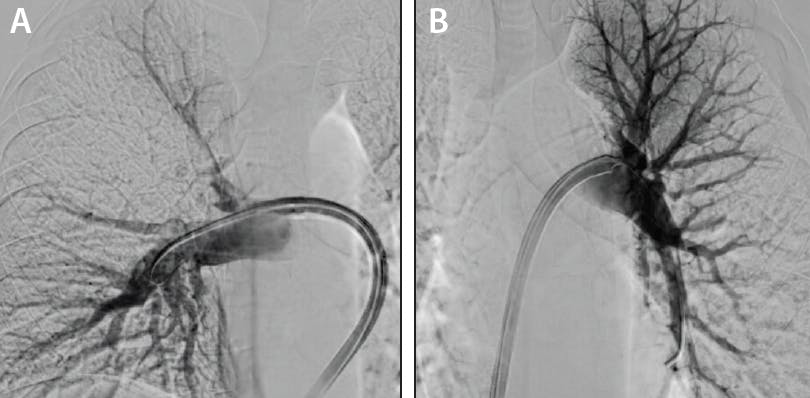

The AVENTUS Thrombectomy Catheter was advanced over the integrated 5-F navigation catheter on an Amplatz wire into the PA (Figure 2). Its soft, atraumatic tip enabled smooth advancement without a dilator. A right pulmonary angiogram was performed directly through the system. Upon engaging clot, the catheter’s real-time TrueClot™ Sensing indicator changed color, confirming optimal alignment for aspiration. A single, targeted angiographic run was obtained to confirm large central thrombus in the right main PA with near-complete obstruction of lobar and segmental branches, correlating with the findings of CTPA.

Figure 2. Minimal baseline angiography was necessary due to utilization of real-time TrueClot™ Sensing technology. A single, targeted angiographic run was obtained to confirm large central thrombus in the right main PA with nearcomplete obstruction of lobar and segmental branches, correlating with the findings of CTPA. Additionally, we decided not to do a pulmonary angiogram on the left side.

The in-line blood return system allowed real-time visualization of aspirated thrombus (Figure 3) and delivered negligible blood loss. Total contrast volume was approximately 50 mL. Completion angiography showed near-complete restoration of bilateral perfusion (Figure 4). Postprocedure PA pressures were 21/11 mm Hg. Total device time was 22 minutes with no arrhythmia, vascular injury, or hemodynamic instability.

Figure 3. Post-thrombectomy pulmonary angiography demonstrating restored bilateral perfusion with minimal residual thrombus. Right PA angiogram demonstrated significantly improved opacification of segmental and subsegmental branches, with only minimal distal residual thrombus (A). Left PA angiogram showing near-complete resolution of previously occlusive thrombus, with brisk and homogeneous enhancement of the lower lobe vascular bed and restored downstream perfusion (B).